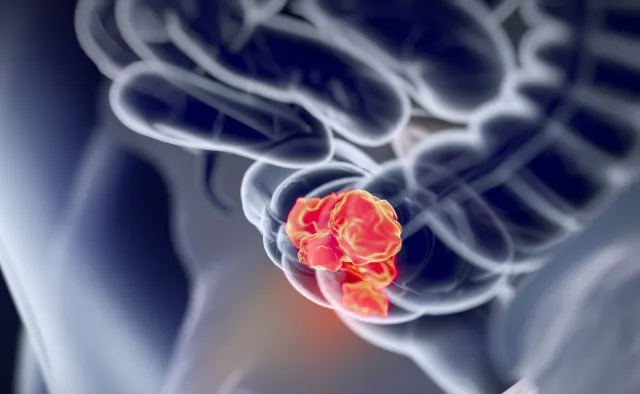

Ministerstwo Zdrowia wraz z Agencją Oceny Technologii Medycznych i Taryfikacji prowadzi działania mające na celu wypracowanie kompleksowego leczenia raka płuc, piersi, jelita grubego, prostaty i narządów kobiecych – poinformowała podczas posiedzenia senackiej komisji zdrowia wiceminister zdrowia Katarzyna Głowala. W Polsce jest bardzo niska pięcioletnia przeżywalność osób chorych na raka. Pięć lat przeżywa zaledwie 10-15 procent pacjentów.

Wyjaśniła, że z powodu braku kompleksowej diagnostyki i leczenia wiele procedur trzeba powtarzać. Z danych NFZ wynika, że na przykład w 2014 roku hospitalizowanych było 62 tysiące osób cierpiących na raka płuc, z czego 43 procent powtórnie. Jedną z przyczyn była między innymi konieczność powtórzenie procedur diagnostycznych. Ponieważ w niektórych przypadkach na diagnostykę specjalistyczną trzeba czekać 160 dni, wcześniej przeprowadzone badania, na przykład tomografię komputerową, należy wykonać jeszcze raz.

Prof. Chorostowska-Wynimko poinformowała, że w Polsce jest bardzo niska pięcioletnia przeżywalność osób chorych na raka. Pięć lat przeżywa 10-15 procent pacjentów. Profesor podkreśliła, że jedynie leczenie chirurgiczne daje dużą szansę na całkowite wyleczenie. Do tego rodzaju terapii kwalifikuje się jednak zaledwie 20 procent chorych. Jednym z głównych powodów jest późne diagnozowanie choroby nowotworowej płuc. – – powiedziała profesor doktor habilitowany nauk medycznych Halina Batura-Gabryel, krajowy konsultant w dziedzinie chorób płuc. To od nich w dużej mierze zależy prawidłowa diagnoza, a co za tym idzie – szybkie wdrożenie terapii.